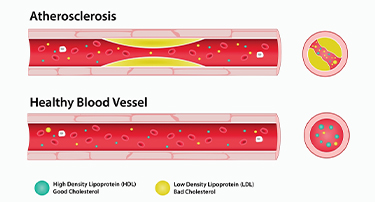

10 Natural Ways to Lower Cholesterol and Improve Heart Health

Although elevated cholesterol can cause health problems, it is necessary for several vital body processes. Exercise and dietary changes may help lower cholesterol, but some people will also require medication. All of the cholesterol required by the body is naturally produced by the liver. However, the liver can manufacture more cholesterol when some foods are consumed, while other foods include cholesterol. The National Heart, Lung, and Blood Institute states that the main cause of high cholesterol is unhealthy lifestyle choices. You can enhance the armada of fats in your bloodstream and reduce your bad cholesterol by making right dietary changes. The easiest strategy behind a low cholesterol diet is to include foods that reduce LDL, the dangerous cholesterol-carrying particle that causes artery-clogging atherosclerosis.

Good vs. Bad Cholesterol: What You Need To Know About HDL And LDL

Cholesterol is a vital substance in the body, yet its role is often misunderstood. While it is essential for building cells and producing hormones, an imbalance can lead to serious health issues. Understanding the difference between good and bad cholesterol—HDL and LDL—is crucial for maintaining heart health and overall well-being. This article delves into the types of cholesterol, their effects on the body, and how to manage them effectively.

How to Reduce Cholesterol by Food: Cholesterol Reducing Foods

Cholesterol is a type of fat that is produced by the liver and also absorbed from the foods we eat.Cholesterol plays a crucial role in forming cell membranes and producing hormones, essential for various bodily functions.However, an imbalance in cholesterol, especially with high levels of LDL (low-density lipoprotein), can lead to serious health risks, such as heart disease, stroke, and other cardiovascular issues.